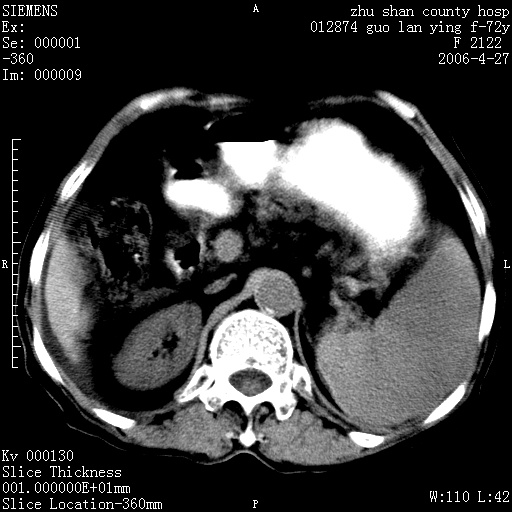

平扫所见:胆囊区两点壮高密度影,灶周有伪影{请问楼主患者有手术病史?}。肝实质内未见明显异常{建议强化或mri}.腹腔有少量积液,脾明显增大.右肾形态似不规则?

腹腔内示积液征,脾脏略增大,肝脏由于运动伪影较多,影响观察,内未见明显高密度区,胆囊内示两处高密度结石。胃窦部壁轻度增厚。另外,肝脏的前缘似有游历气体。不知病人的临床如何?有必要做胃的检查,还有,看看骨窗是否有腹腔游离气体还是肠管影响的。

肝脏缩小,脾脏增大,肝脾外缘及胆囊窝液性密度影,肝脾ct值正常,胆囊区见两个类圆形高密度影,下腔静脉前方类圆形软组织密度影为肝脏岛叶,胃幽门区见软组织密度影,十二指肠钡剂充盈不好.

1:腹水2:胆囊结石3肝硬化?(不确定,请结合临床)4幽门区占位?(建议胃肠透视)

肝硬化,脾大,少量腹水

肝硬化、腹水、脾大,胆囊结石可以肯定。只是肝右叶两个低密度有必要增强确定一下;排除小肝癌。

谢谢牟教授在百忙之中还认真的点评我的帖子!也谢谢大家的鼎力相助,此病人是我们医院护理部主任的母亲!病人以前无特别不舒适!昨天b超后发现有问题!做ct的目的在于排除肝内占位性病变,此病人以前无手术外伤史.